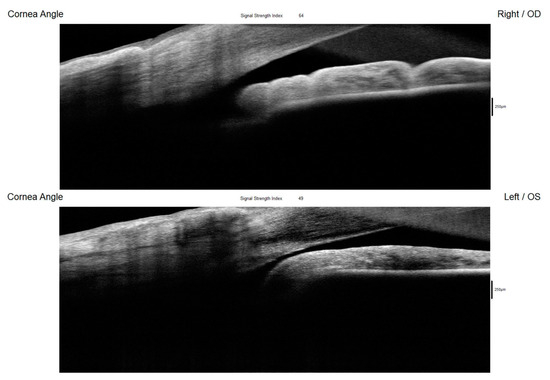

Figure 5. The AS-OCT (RTVue, Optovue Inc., Fremont, CA, USA) offered comprehensive imaging of the anterior segment structures, primarily emphasizing the cornea and corneal angle. While it also visualized the iris, its capability for retroiridian imaging was limited, preventing assessments of this space. The device revealed a narrow and closed angle in the left eye (Figure 5). This finding aligns with the results obtained from gonioscopy and UBM, which similarly indicated a compromised angle configuration. Figure 5 shows AS-OCT of the right and left eyes showing an open corneal angle in the right eye (upper picture) and a closed angle in the left eye (lower picture) resulting from the posterior displacement of the ciliary body cysts. OD: right eye; OS: left eye.